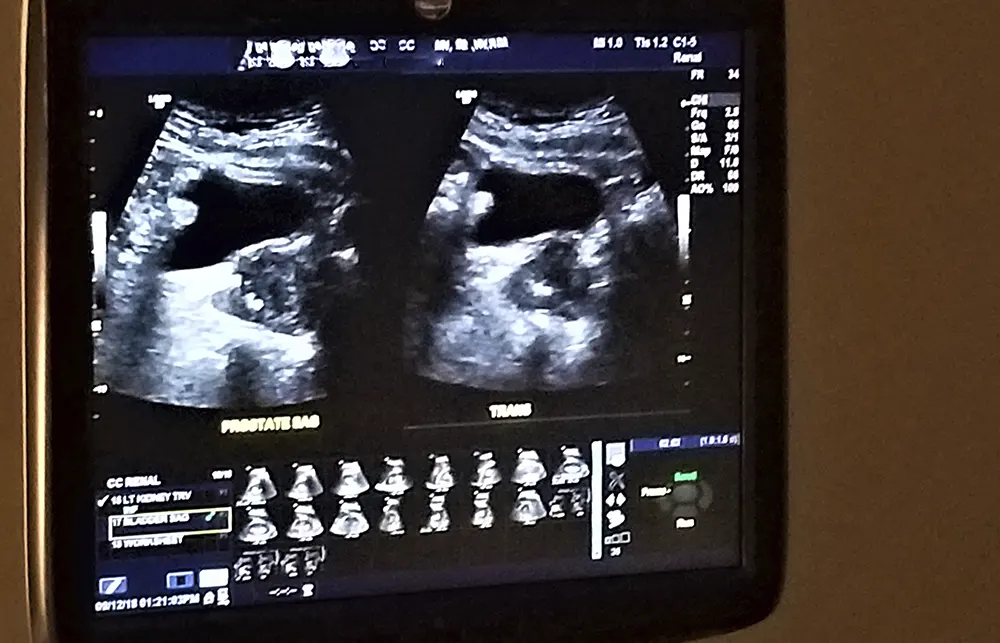

Nefrologia

A área da medicina que estuda o funcionamento normal e as doenças que acometem os rins é a Nefrologia.

Os rins são dois órgãos localizados na região posterior do abdome e considerados vitais para a nossa sobrevivência. São responsáveis por diversas funções no nosso organismo como, filtrar o sangue mantendo o equilíbrio dos seus elementos, eliminar as impurezas que são frutos do metabolismo, regular a pressão arterial e produzir hormônios que estimulam a produção de sangue (evitam anemia) e que regulam a saúde dos ossos (metabolizam a vitamina D).

O médico que se especializa em doenças que acometem os rins é o Nefrologista e as condições mais frequentes no seu dia a dia são a Doença Renal Crônica (DRC), Injúria Renal Aguda (IRA), nefrolitíase (cálculo renal/pedra nos rins), hipertensão arterial, doença císticas renais e as glomerulopatias.